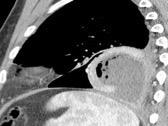

Naidich DP et al. Computed tomography of the diaphragm: peridiaphragmatic fluid localization.J Comput Assist Tomogr1983.

En el corte axial, el líquido pleural se sitúa por detrás